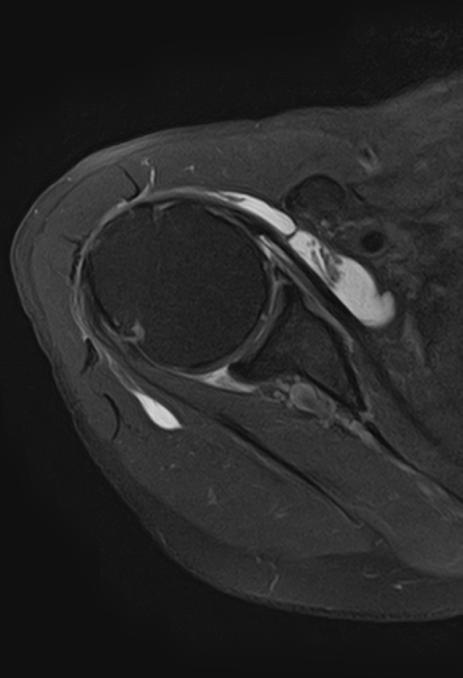

Coronal PD FatSat of the Shoulder, Res: 0.3 x 0.3 x 3 mm, Scan time: 3:25 Original. Same image after AiCE Reconstruction.

Shoulder

16ch Flex SPEEDER, PD, AiCE + Compressed SPEEDER, Res: 0.3 x 0.3 x 3 mm, Scan time: 3:23 min.

Shoulder scanned with Shoulder SPEEDER Coil

- Axial PD with FatSat

- Resolution: 0.6 x 0.6 mm

- Slice thickness: 3 mm